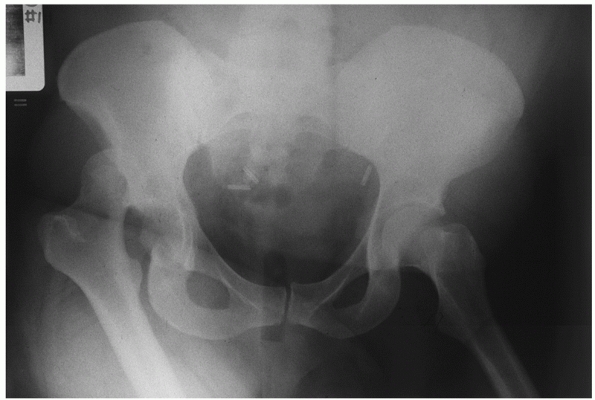

(AP) pelvis radiograph. This is usually taken as part of the initial

apparent on this single radiographic view (Fig. 46-4).

The key to the diagnosis on the plain AP pelvis is the loss of

congruence of the femoral head with the roof of the acetabulum. On a

true AP view, the head will appear larger than the contralateral head

if the dislocation is anterior and smaller if posterior. The most

common finding in the case of a posterior dislocation is a small head

that is overlapping the roof of the acetabulum. In an anterior

dislocation, the head may appear medial to or inferior to the

acetabulum.

rotation is also detectable on the single AP view. The lesser

trochanter is more apparent and the femoral neck is seen in profile

when the femur is internally rotated (see Fig. 46-4).

![]() |

FIGURE 46-4 The trauma AP pelvis radiograph of the patient in Fig. 46-2

demonstrates a posterior dislocation of the right hip. Note the superior location of the femoral head and the internally rotated proximal femur. |